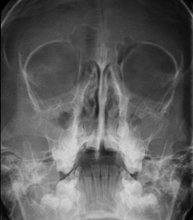

Técnica mediante la cual, utilizando rayos X, se obtienen imágenes del cráneo para su estudio. Indicaciones: traumatismo, cierre precoz de suturas craneales. - RX Senos Paranasales

Técnica mediante la cual, utilizando rayos X, se obtienen imágenes de los senos paranasales para su estudio. Indicaciones: dificultad respiratoria nasal, tos crónica, cefalea, mucosidad. - RX ATM (Articulación Temporo-Mandibular)